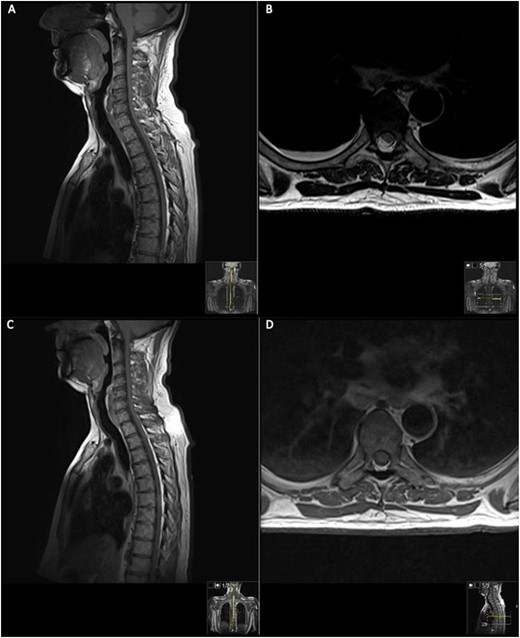

The patient was started on methylprednisolone (1 g/day) for 3 days under the neurology team; however, this did not improve his neurological status, and subsequently, his neurology progressively worsened to a lower limb weakness to an MRC grade of 1/5 bilaterally with faecal incontinence. A second MRI spine was performed with contrast (Fig. 2).

Repeat contrasted MRI whole spine; demonstrates findings consistent with spinal cord meningioma at the level of T6; this can be clearly visualized by comparing the T1 sagittal pre-contrast (A) with a T1 sagittal post-contrast (B), where a clearly demarcated lesion can be seen at the level of T6; this is supported further by the sagittal T2 image (C) shown where an ~24 mm lesion can be seen at T6.